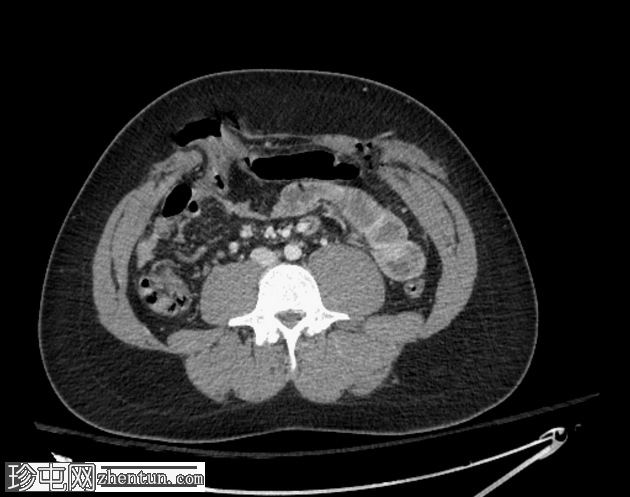

轴位增强扫描(门静脉期)

气腹伴复杂性腹膜积液,提示全层肠损伤。

前腹壁多处刺伤,横结肠和肠系膜经右侧和左侧腹直肌鞘中部疝出。

左侧后方分层血胸。

CT是钝性及穿透性创伤的首选

影像

学检查方法。本例中,腹壁软组织缺损和肠疝清晰可见。